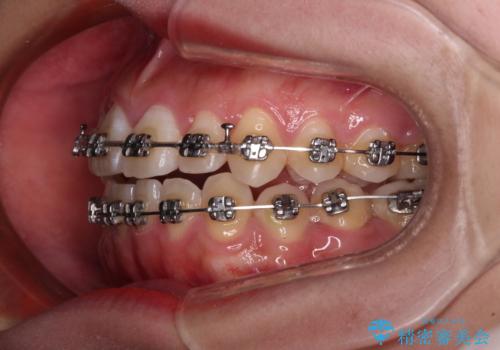

- 矯正装置

- メタルブラケット

上顎歯列が狭窄していたため、急速拡大装置により上顎骨を側方に拡大し、その後ワイヤー装置にて矯正治療を行うこととしました。

上顎骨を拡大することで、八重歯やデコボコを歯列に収めることができ、下顎の歯が外に位置していた奥歯の咬み合わせも改善することができました。

スペースも短期間に獲得できるため、1年程度で治療を終えることができました。